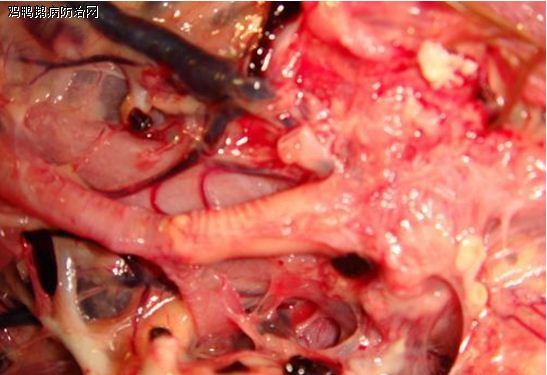

6.1.2 剖检变化

6.1.2.1肺水肿。主要表现呈肺实变,缺少气体,切面出现带有泡沫的渗出液。

6.1.2.2肾水肿。肾肿胀多呈红至紫红、深红色,间质加宽可呈条网状分割样变化。

6.1.2.3心脏扩张。从锥形变成倒桃形,如同双人合臂围成的爱情心。严重的可见心包积液。

6.1.2.4气管通常病变轻,多是良好的,支气管栓塞常见,同时肺内小支气管甚至肺泡内都可见白色或黄色的大小不同干酪样栓塞。

缺氧时上述病变一定会出现。